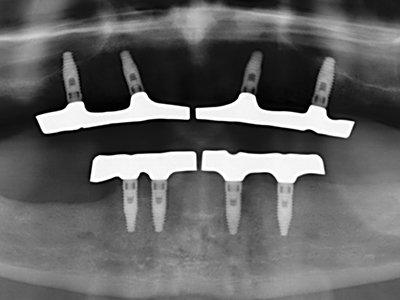

Como ya se ha demostrado en el pasado, básicamente cualquier procedimiento de cirugía de hueso representa una posible indicación para la cirugía piezoeléctrica. Así, la preparación del segmento móvil en la osteogénesis de distracción (fig. 23-25) y en la osteotomía de sándwich puede realizarse con piezas especiales, sin poner en peligro el suministro sanguíneo de la parte crestal, que resulta esencial para el éxito de ambas técnicas (González-García, Diniz-Freitas et al. 2008).

Para la extracción de implantes es posible realizar la preparación de una tapa ósea vestibular que, tras retirar el tornillo del implante, vuelve a fijarse y, de este modo, mantiene el contorno de la apófisis alveolar.

En la cirugía del seno maxilar surgen otros campos de aplicación: En este punto, tras la preparación concéntrica de una tapa ósea de la pared del seno maxilar (que suele tener forma trapezoidal), es posible eliminar patologías y cuerpos extraños del seno maxilar. La tapa ósea se repone después de finalizar la parte intra-antral de la operación y se asegura frente a una posible dislocación mediante cuñas o suturas adaptables.